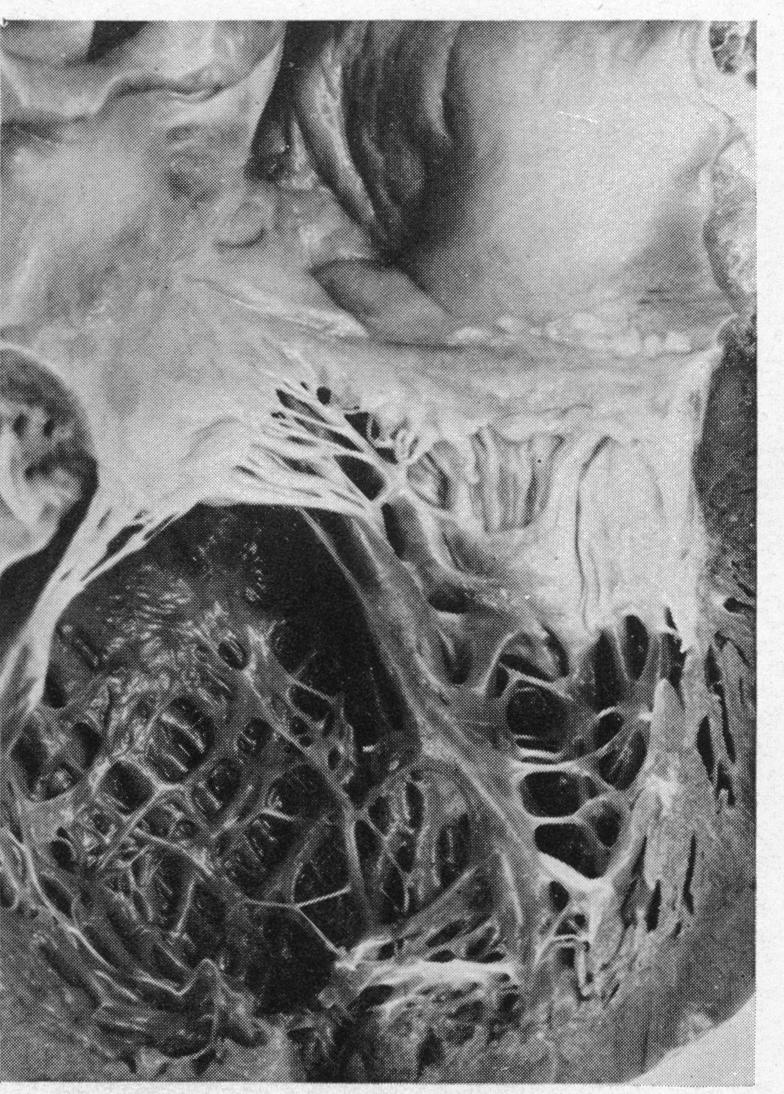

DAVIES J N, BALL J D

Br Heart J. 1955 Jul;17(3):337-59. doi: 10.1136/hrt.17.3.337.